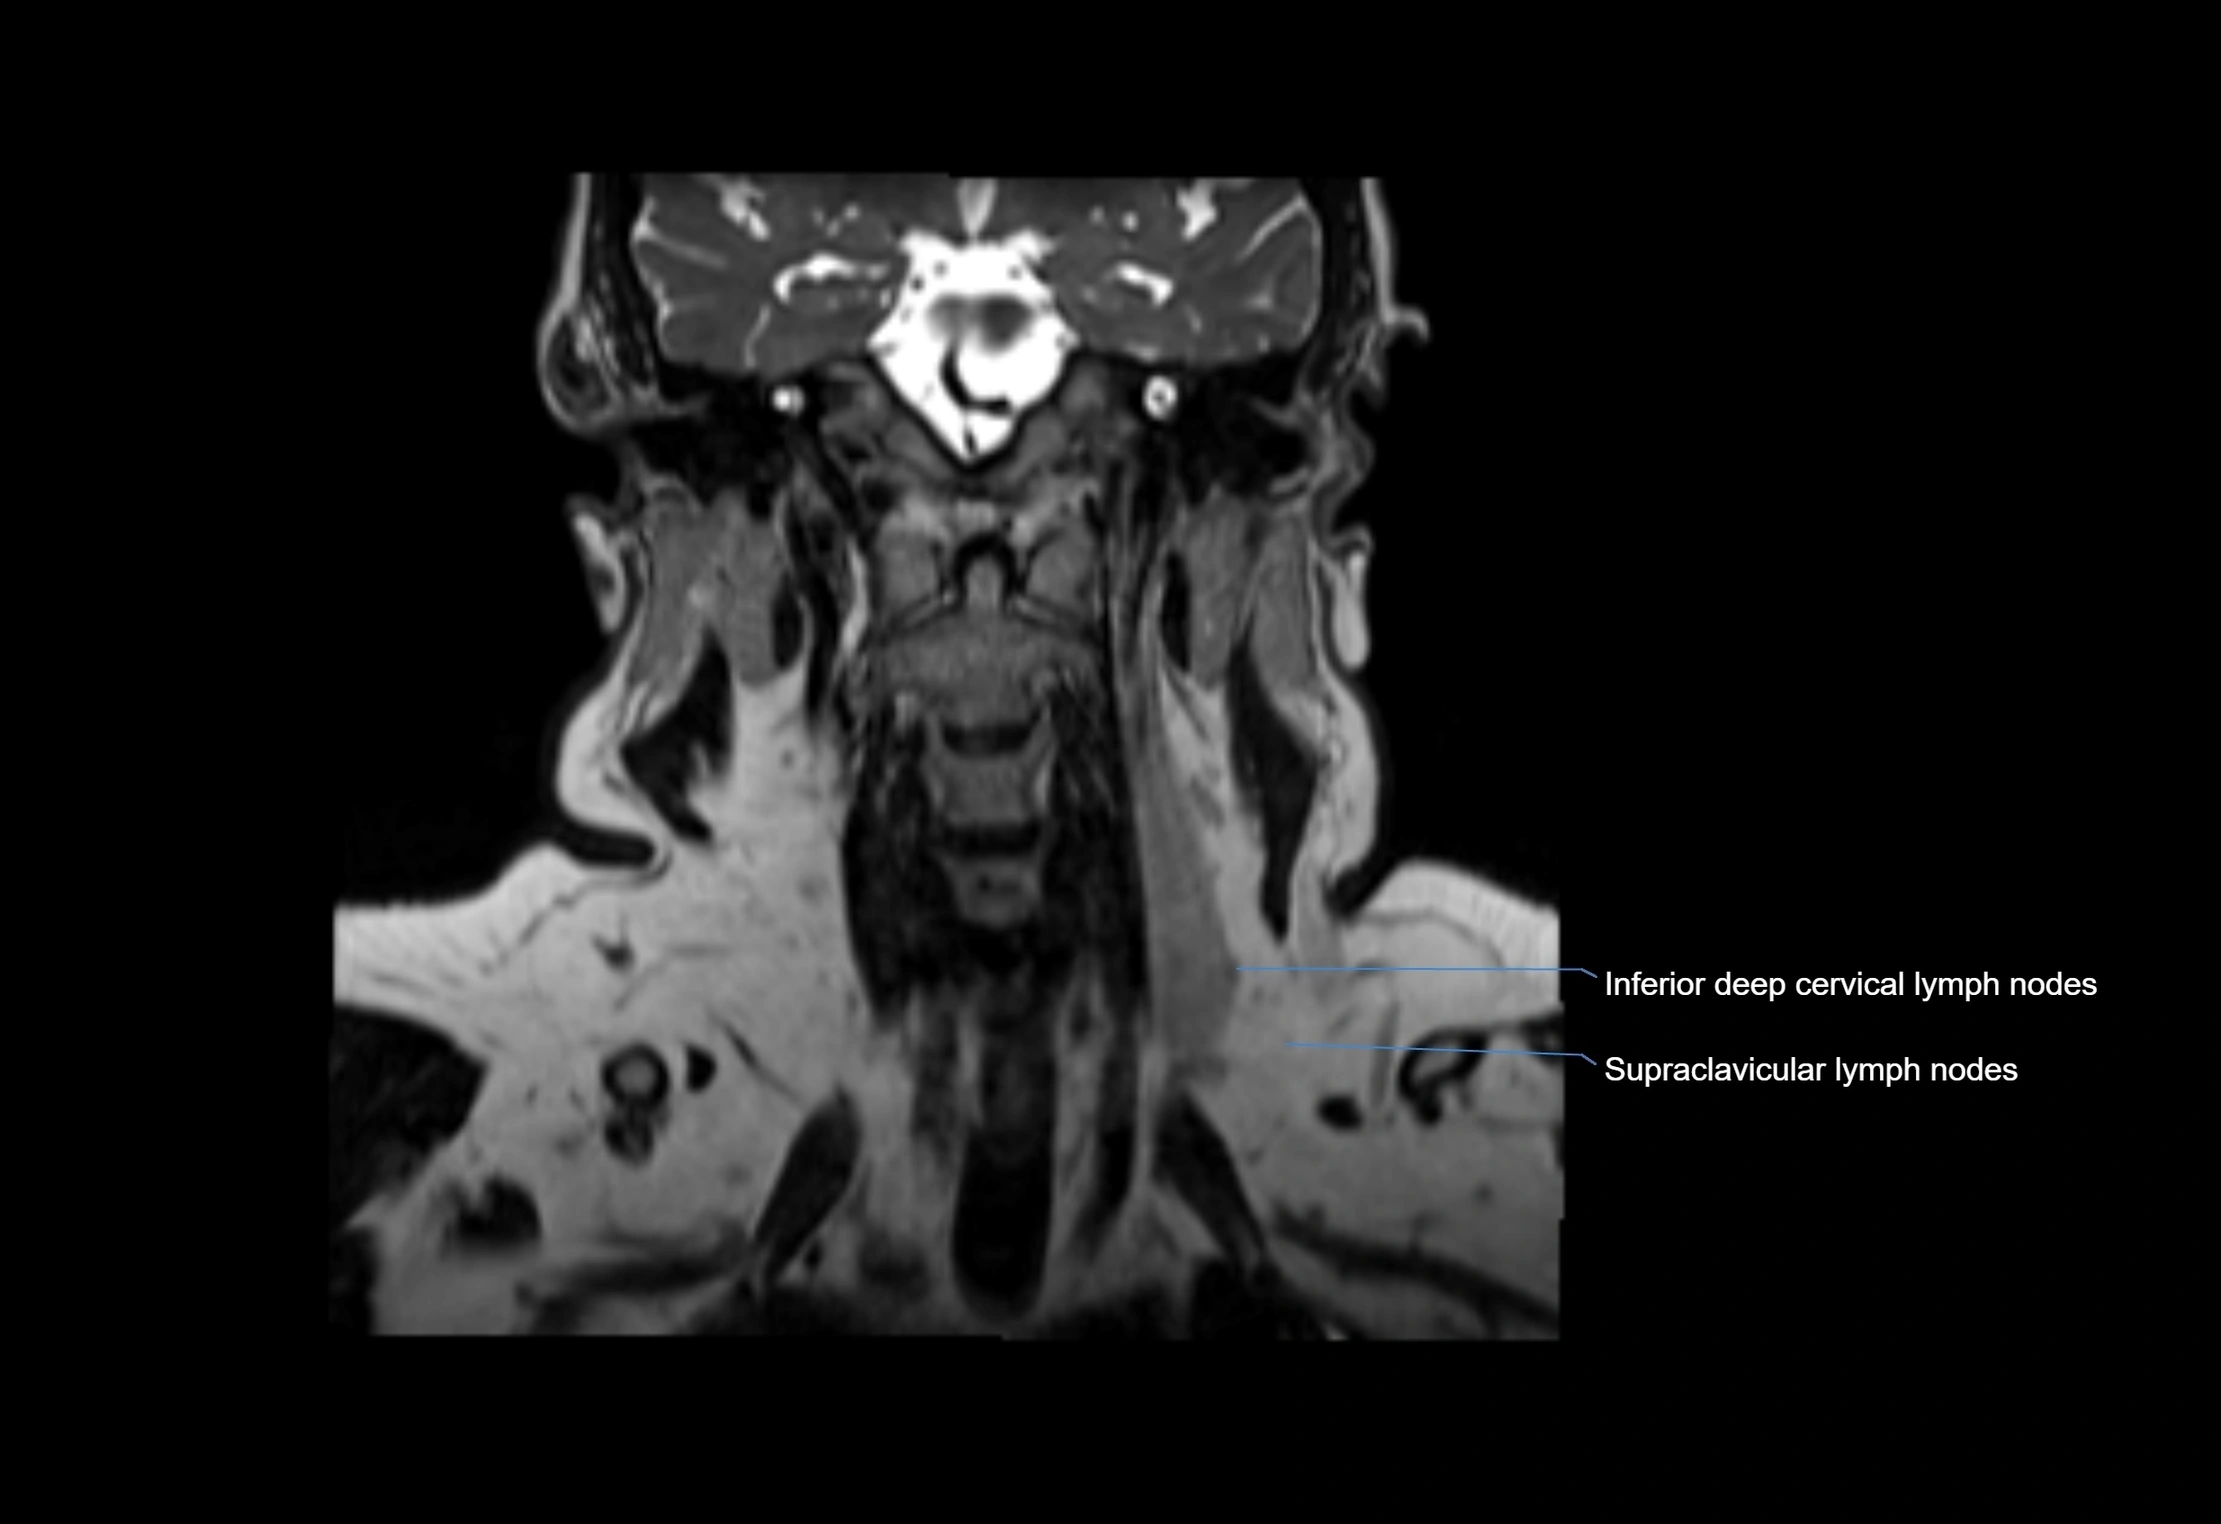

MRI images

image